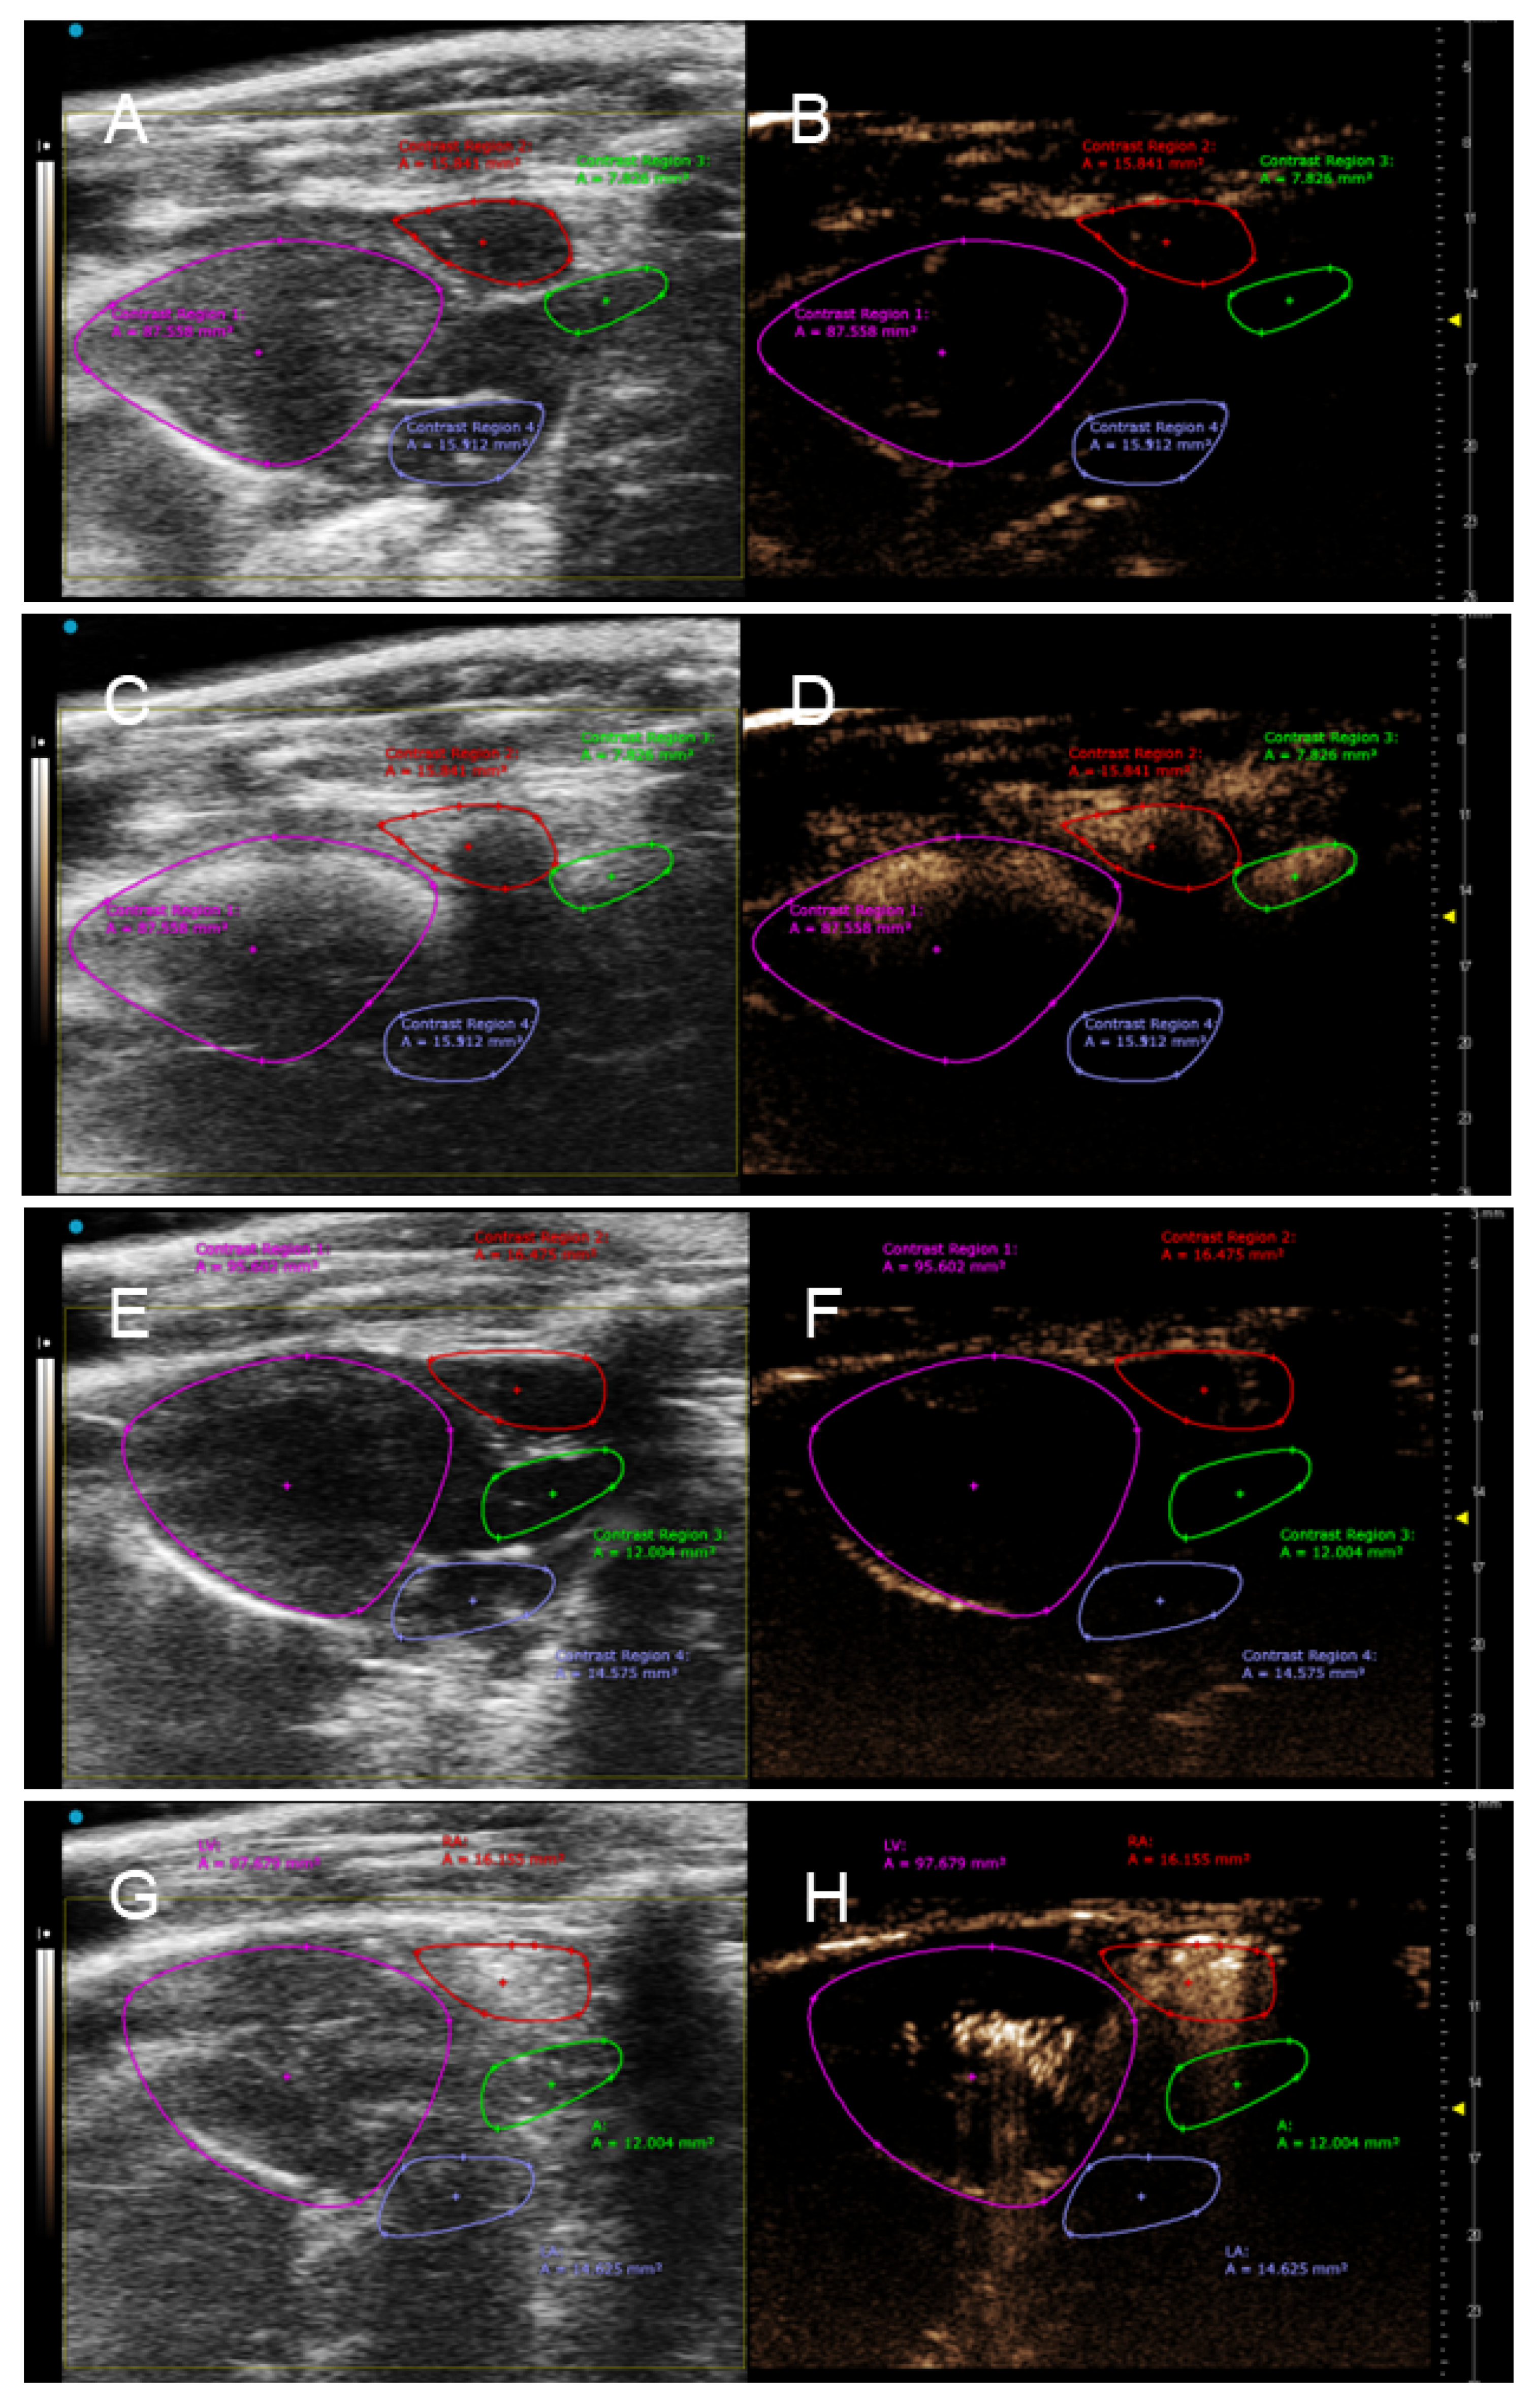

3.2. In Vivo NLC Imaging of Rat Heart